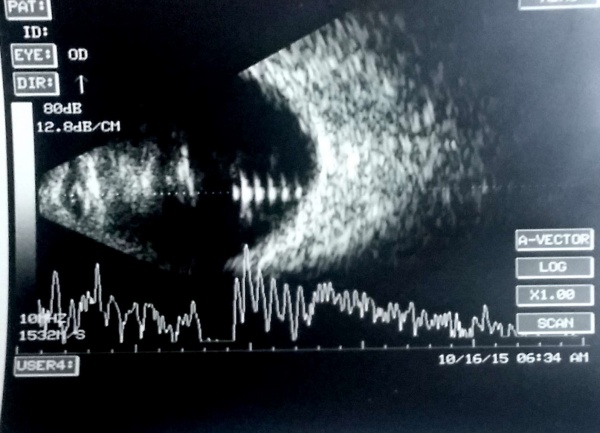

Retained lens material (posterior dislocation of lens fragments)

After posterior capsular rupture with dropped lens material in the vitreous cavity, the USG locates the lens material and gives an idea of the size of the lens fragments. The lens matter appears as a lesion in the vitreous cavity (usually inferiorly) with moderate to high amplitude which moves on ocular movement.